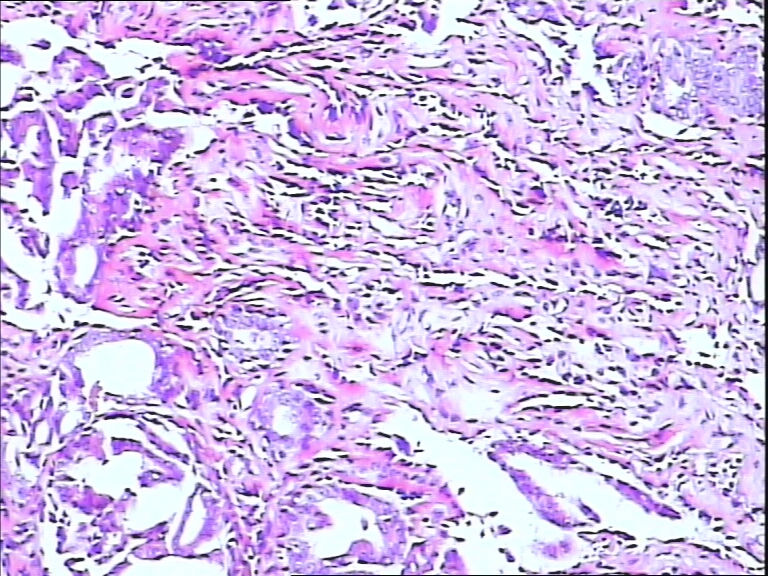

B3785左乳头包块!

42y

左乳头有3mm结节

灰白不整形组织一块:0.7*0.5*0.4

• 左乳头包块!图2

图2

标签:导管内乳头状肿瘤

导管内乳头状瘤

乳头腺瘤(nipple duct adenoma)或称乳头的乳头状瘤

导管内乳头状结构,细胞无异型性,诊断导管内乳头状瘤。